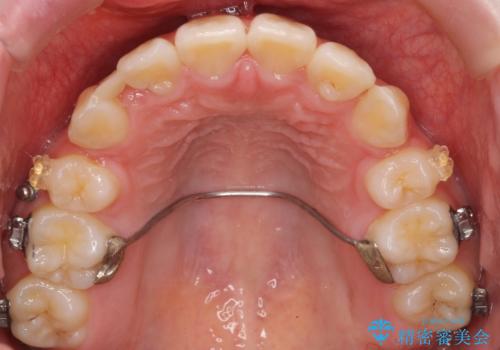

- 矯正装置

- 審美装置

成人式の1年前から矯正をはじめ、成人式前に上の前歯の装置を一時的にとりました。

一時的に装置を取ることで、多少治療期間が伸びましたが、それでも、2年かからずに外すことができました。